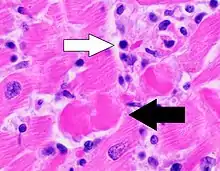

| A microscope image of myocarditis at autopsy in a person with acute onset of heart failure | |

The gold standard is the biopsy of the myocardium, in general done in the setting of angiography. A small tissue sample of the endocardium and myocardium is taken and investigated. The cause of the myocarditis can be only identified by a biopsy. Endomyocardial biopsy samples are assessed for histopathology (how the tissue looks like under the microscope): myocardial interstitium may show abundant edema and inflammatory infiltrate, rich in lymphocytes and macrophages. Focal destruction of myocytes explains the myocardial pump failure.[10] In addition samples may be assessed with immunohistochemistry to determine which types of immune cells are involved in the reaction and how they are distributed. Furthermore, PCR and/or RT-PCR may be performed to identify particular viruses. Finally, further diagnostic methods like microRNA assays and gene-expression profile may be performed.